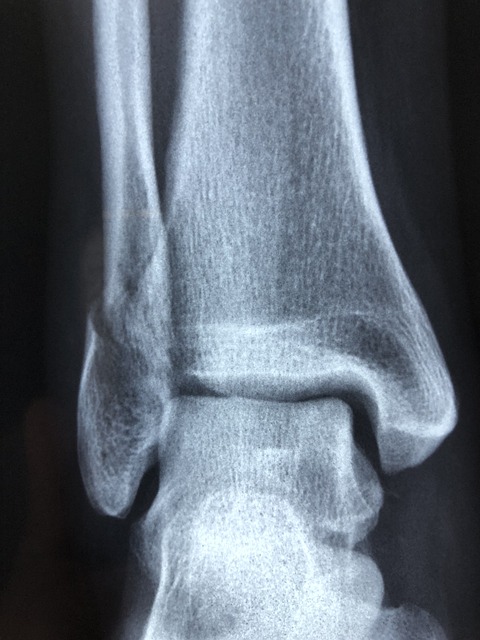

- 정량적 초음파: 종종 발뒤꿈치에 적용되는 음파를 사용하여 골밀도를 측정하는 예비 검사 방법입니다.

3) 잦은 골절

특히 엉덩이, 손목, 척추의 뼈는 사소한 넘어짐이나 약간의 충격에도 쉽게 부러질 수 있습니다.